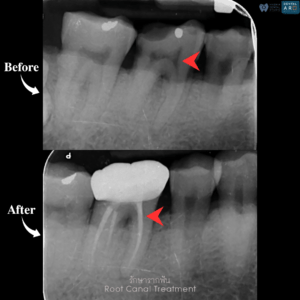

รักษารากฟัน

คือ การรักษาฟันที่เกิดการอักเสบและติดเชื้อภายในโพรงประสาทฟัน และเนื้อเยื่อรอบปลายรากฟัน อันมีสาเหตุมาการอักเสบและติดเชื้อภายในรากฟัน โดยทันตแพทย์จะทำการทำความสะอาดและใส่ยาในคลองรากฟัน และทำการอุดรากฟันเป็นขั้นตอนสุดท้าย การรักษารากฟันจะช่วยเก็บรักษาฟันให้สามารถคงอยู่ในช่องปากต่อได้ โดยไม่ต้องถอนฟันและไม่ต้องใส่ฟันทดแทน